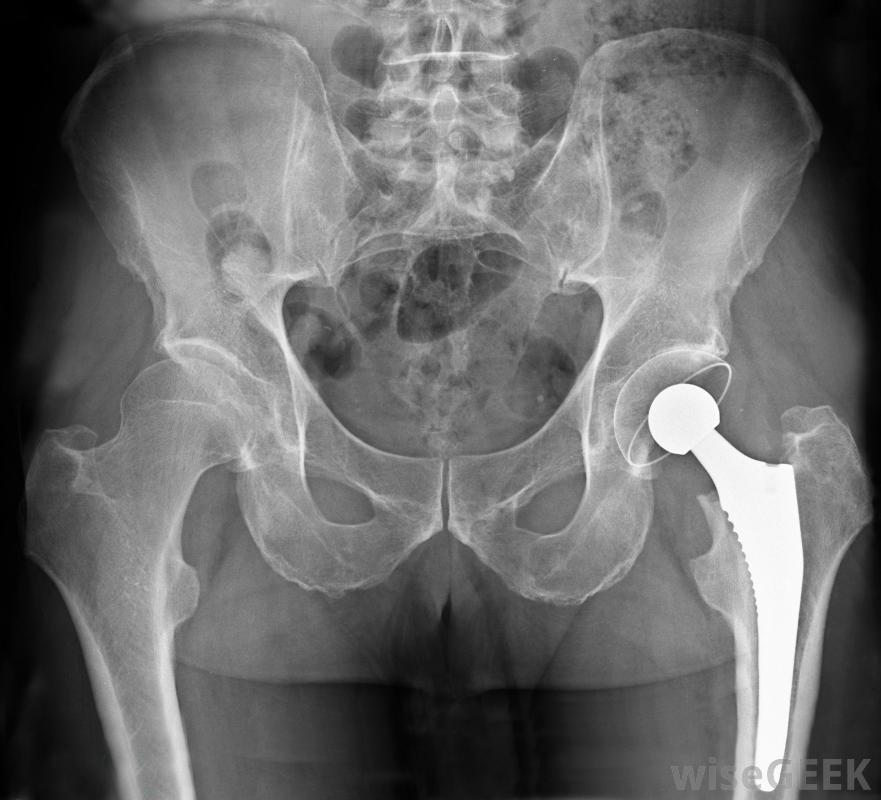

骨水泥是髋关节置换手术中使用的一种物质,它作为粘合剂将人工髋关节固定在适当的位置。它可以是预先混合的形式,也可以是手术过程中在手术室中混合的粉末和液体。骨水泥也可以用来填充骨头上的任何洞或裂缝,并且可能含有抗生素来防止感染。一旦混合,粘合剂就会变成糊状或糊状物质,在几分钟内凝固。骨水泥用于髋关节置换手术,将腿部股骨头固定在人工髋关节上骨水泥的性能由聚甲基丙烯酸甲酯(PMMA)组成。这种塑料也用于不易破碎的玻璃、浴缸,它是髋关节置换术中的一种标准粘合剂,用于将腿的股骨头连接到人工髋关节上。用这种物质进行的髋关节置换手术通常可以使用几十年骨骼解剖图。外科医生也在椎体成形术中使用骨水泥来治疗骨质疏松症医生用x光片和一个观察屏幕来确定将密封剂注入脊柱的针头的位置。在这个过程中,粘合可以减轻骨质疏松引起的压缩性骨折引起的疼痛2010年,研究人员资助了人体试验,探索骨水泥用于修复退伍军人头部和面部的损伤。一种能促进骨生长的物质可以注入骨水泥中,从而消除了用金属板修复骨折的必要性。这种粘合剂的使用也可能对骨折的胳膊和腿起作用在事故中骨折。当抗生素加入骨臼时,它有助于减少感染。细菌感染会阻碍骨骼的再生,如果暴露在空气中的开放性骨折被某些细菌侵入,可能会导致截肢。动物研究表明,在加入特定抗生素后,将这种产品注射到骨折处可以防止葡萄球菌感染心脏外科医生在心脏直视手术后使用非合成骨水泥来封闭胸骨。聚合物骨水泥由蓖麻籽中的甘油三酯和氯化钙组成,心脏手术后的疼痛大多来自于打开胸骨进入心脏,心脏通常用金属丝封闭。使用骨水泥后,胸骨通常在24小时后完全稳定心脏外科医生在心脏直视手术后使用非合成骨水泥封闭胸骨。